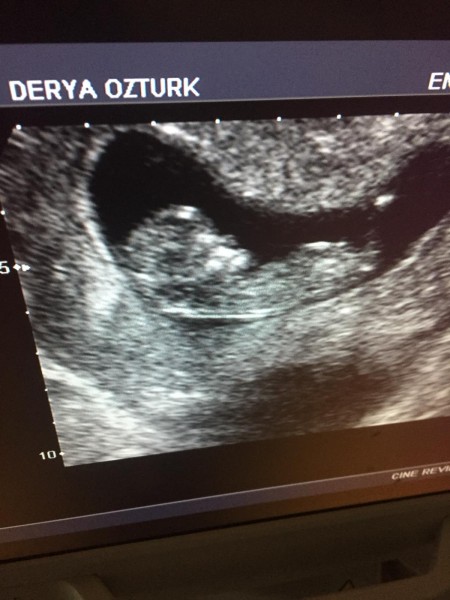

12. Haftadayiz. Kese fasulye şeklinde ise erkek yuvarlak ise kız diyorlar doğru mu ?

Gebelik haftası 12

Erkek bebeğe benziyor canım benimde aynen böyle cinsiyet erkek dedi doktorum hayırlı evlat olsun inşallah öncelikle hepimiz için

Ne kadar dogru bilmiyorum ama bebisin erkege benziyo canim

Kese teorisi diye bir şey var canım ama kese şekli ile belli olmuyor bebeğin keseye nereden girdiğine bakılıyor. Yalnız bebeğin oğlan gibi geldi bana da

Cinsiyetini öğrenince net yazar mısın çünkü pozisyonu ve sürat surat ifadesi aynı bu haftada benim bebeğim gibi ve bizim Erkek

Büyük olasılıkla erkek